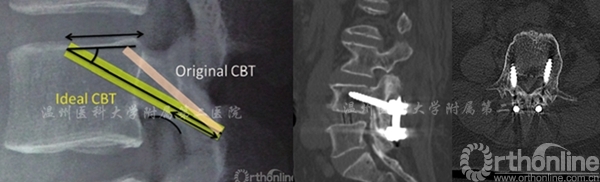

2009年,一种全新的内固定置入技术首次被提出,通过椎弓根在横断面上由内向外、矢状面由下向上置钉,为了与传统椎弓根置入技术区别,称之为经皮质骨轨迹(cortical bone trajectory,CBT)螺钉技术[1]

CBT螺钉置钉点较传统椎弓根螺钉更偏内、偏下,靠近峡部,暴露更容易,能减少软组织的剥离程度。此外,CBT螺钉可与植入点背侧皮质骨、椎弓根后内侧壁、前外侧壁及椎体壁做到四点接触,进而显著提高螺钉的把持力(图1)。

与传统椎弓根螺钉相比,CBT技术采用的螺钉具有更小的直径、更短的长度,并且螺纹排列更紧密,从而增加与骨皮质的接触面积,增加螺钉的强度及稳定性;另外,CBT螺钉轨迹自内而外、由下而上,避开硬膜囊和神经根走行部位,从而降低神经、血管损伤的概率。

图7 左:理想的皮质骨螺钉轨迹 右:不理想的皮质骨螺钉轨迹(螺钉轨迹偏下、偏内)